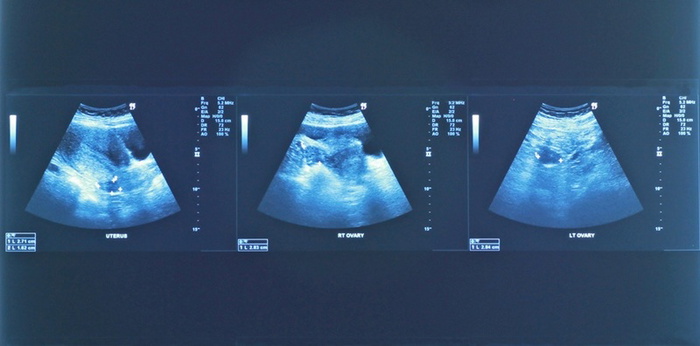

การตรวจอัลตราซาวด์ คืออะไร

การตรวจอัลตราซาวด์เป็นการตรวจทางการแพทย์ที่อาศัยคลื่นความถี่สูงเกินกว่าความสามารถที่หูมนุษย์จะได้ยิน (มากกว่า 20,000 เฮิซร์ต) ส่งคลื่นเสียงผ่านหัวตรวจไปยังอวัยวะที่ต้องการตรวจ เมื่อเสียงกระทบเนื้อเยื่อต่างชนิดกัน ก็จะเกิดการสะท้อนและการดูดกลับของเสียงไม่เท่ากันในเวลาที่ไม่เท่ากันตามระดับความลึกของเนื้อเยื่อนั้นๆ และจะถูกแปลผลให้ปรากฏเป็นภาพบนจอ

การตรวจอัลตราซาวด์ บอกอะไรแม่ท้องได้บ้าง

ในช่วง 3 เดือนแรกของการตั้งครรภ์ การอัลตราซาวด์จะช่วยวินิจฉัยชนิดครรภ์แฝด และประเมินอายุครรภ์ได้อย่างแม่นยำ รวมทั้งช่วยวินิจฉัยความผิดปกติบางอย่าง เช่น ภาวะไม่มีกะโหลกศีรษะได้

เมื่อเข้าสู่ช่วงเดือนที่ 5-6 ของการตั้งครรภ์ การตรวจอัลตราซาวด์สามารถตรวจหาความผิดปกติของโครงสร้างร่างกายทารกในครรภ์ โดยเฉพาะโครงสร้างหลัก ได้แก่ กะโหลกศีรษะ เนื้อสมอง โครงกระดูก แขนขา ทรวงอก เนื้อปอด หัวใจ ผนังหน้าท้อง อวัยวะหลักภายในช่องท้อง ได้แก่ ตับ ไต ความผิดปกติของลำไส้บางชนิด กระเพาะปัสสาวะ และอวัยวะส่วนอื่น เช่น ภาวะปากแหว่ง จำนวนนิ้วมือนิ้วเท้าครบหรือไม่ เป็นต้น